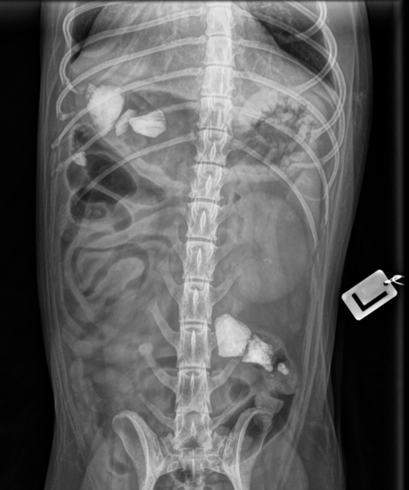

Seuraavaksi Riisi siirtyikin röntgenpöydälle, jolloin syy mahakivulle sekä oksentamiselle paljastui.

Riisin mahassa todettiin röntgentiiviitä kappaleita, tässä tapauksessa kiviä. Osa kivistä oli vielä mahalaukussa, mutta osa oli edennyt jo pidemmälle paksusuoleen asti.